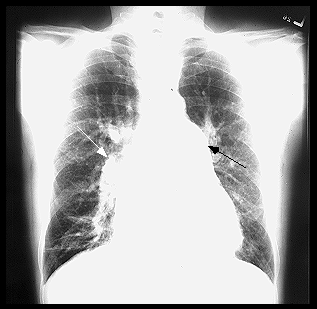

Rx cord-pulmon: circulatie pulmonara 'incarcata' cu ramurile AP dilatate in hiluri si extremitati 'retezate' avind periferie mult mai clara decat normal, bombare a conului arterei pulmonare, semne de hipertrofie VD

HTP secundara incipienta (DSA) HTPS severa (DSA Eisenmengerizat)